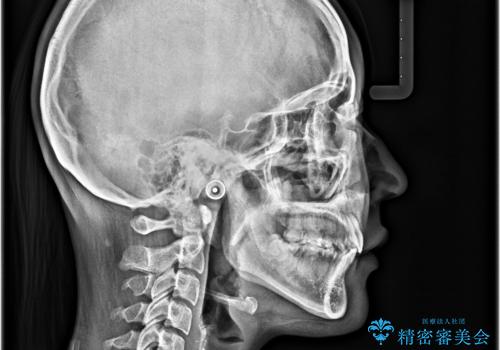

- デコボコになっている前歯を気にして来院された患者様です。

口元の突出感は気になっていないものの、デコボコを解消すると口元が前方に突出する可能性があるため、上下左右の第一小臼歯4本を抜歯して、ワイヤー装置にて矯正治療を行うこととしました。

下の前歯が隠れてしまうほど深く咬みこんでいたため、上顎前歯が前方に突出しているような印象がありましたが、咬み合わせが改善され、整った口元に仕上げることができました。